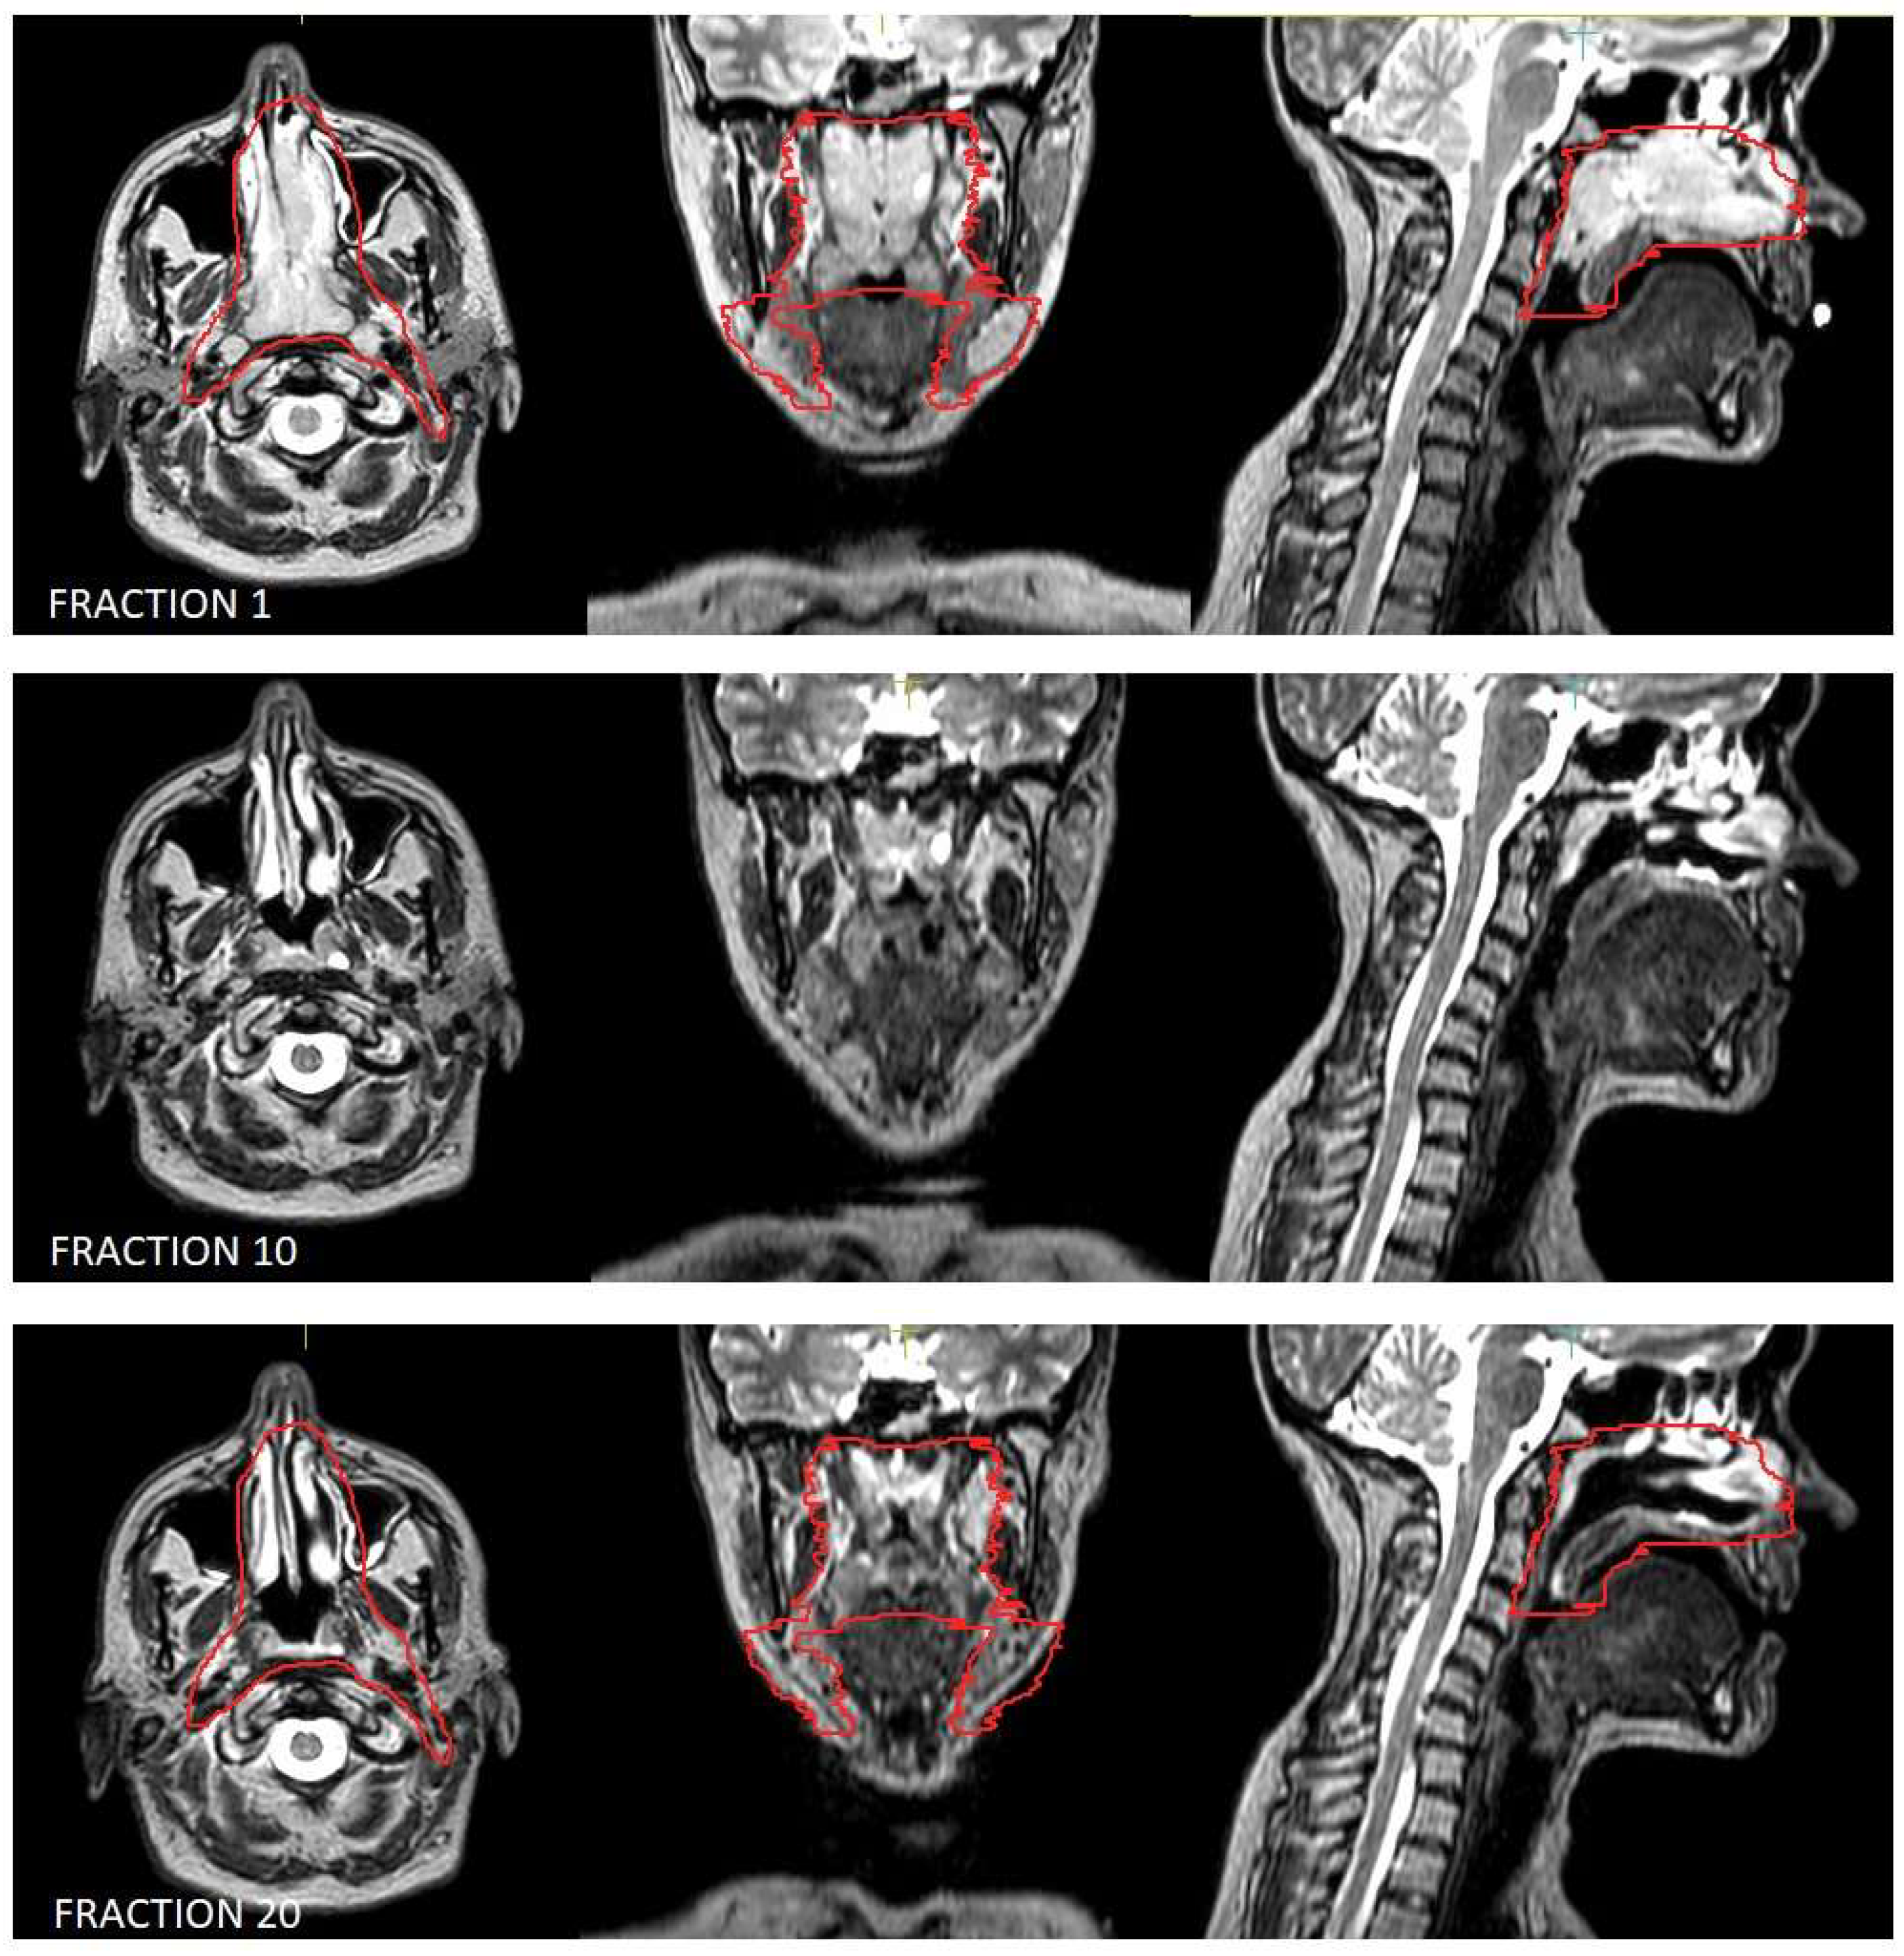

Figure 1.

Volumetric variation in disease in the patient treated for natural killer (NK)/T-cell lymphoma, nasal type. Outlined in red is the clinical target volume.

Moreover, lymphomas are radiosensitive neoplasms that tend to respond early during the course of radiotherapy, often leading to a substantial volume reduction (as exemplified in Figure 1). While “conventional” CT-based image-guided radiotherapy (IGRT) might allow for the detection of major volumetric variations, MRI-based IGRT enables the identification of even slight differences due to improved soft tissue contrast. Moreover, in our cohort every patient was treated using a daily adapt-to-shape workflow, in which contours of the target volumes and OARs are manually edited for each fraction on the basis of daily MR imaging (as exemplified in Figure 2) and the treatment plan is extensively recalculated. The possibility to adapt contours and the treatment plan on the basis of daily MRI scans could improve dose distribution and guarantee optimal target coverage compared with conventional RT, while sparing surrounding organs at risk [21,22]. This should conceptually result in reduced treatment-related toxicity; nonetheless, clinical data to confirm this hypothesis are awaited (also due to the novelty of this technology).